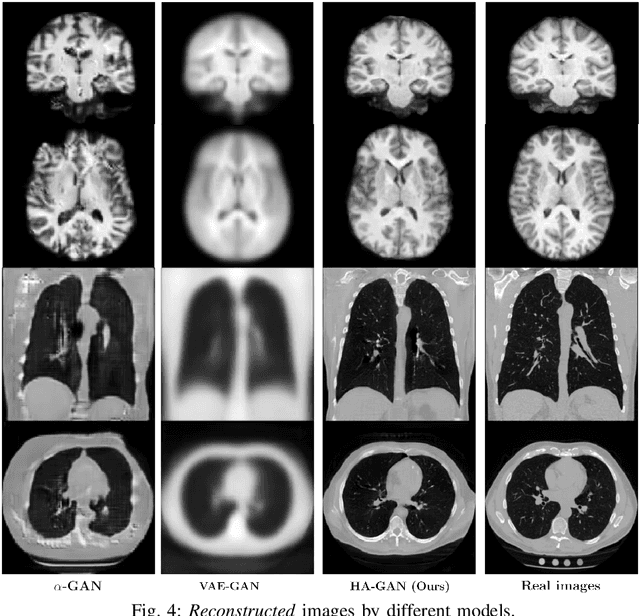

Generative Adversarial Networks (GAN) have many potential medical imaging applications, including data augmentation, domain adaptation, and model explanation. Due to the limited embedded memory of Graphical Processing Units (GPUs), most current 3D GAN models are trained on low-resolution medical images. In this work, we propose a novel end-to-end GAN architecture that can generate high-resolution 3D images. We achieve this goal by separating training and inference. During training, we adopt a hierarchical structure that simultaneously generates a low-resolution version of the image and a randomly selected sub-volume of the high-resolution image. The hierarchical design has two advantages: First, the memory demand for training on high-resolution images is amortized among subvolumes. Furthermore, anchoring the high-resolution subvolumes to a single low-resolution image ensures anatomical consistency between subvolumes. During inference, our model can directly generate full high-resolution images. We also incorporate an encoder with a similar hierarchical structure into the model to extract features from the images. Experiments on 3D thorax CT and brain MRI demonstrate that our approach outperforms state of the art in image generation, image reconstruction, and clinical-relevant variables prediction.